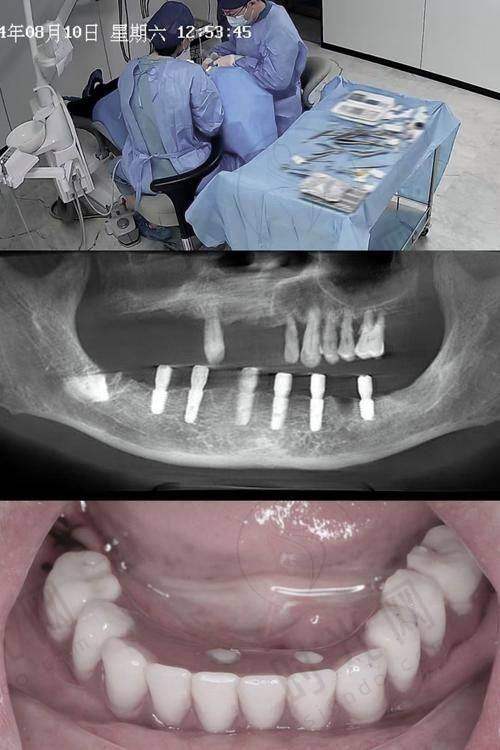

这就是2025年牙科更火的“即拔即种技术”(也叫“即刻种植”)!传统种牙像“先拔牙、等伤口长好(3个月)、再种牙根、再等3个月装牙冠”,前后半年才能用;而即拔即种就像“拔树的同时马上栽新树”,拔牙、种牙根、装临时牙冠一步到位,更快2小时完成,当天就能吃饭

【技术突破】3D导航+生物骨粉,实现“精细种植”

2025年的即拔即种有两大升级:

- AI导航种植:术前拍CBCT(口腔CT),电脑自动规划种植角度和深度,误差<0.1mm,避免损伤神经和血管;

- 仿生骨粉填充:拔牙后在牙槽骨缺损处填入“人工骨粉”(成分和人体骨头几乎一样),再植入种植体,骨粉3个月内会和自身骨头长在一起,就像给新牙根“铺了层肥沃的土壤”。

【真实实例】65岁李叔叔即拔即种后当天吃馄饨

李叔叔左上磨牙松动3年,牙根都露出来了,医生检查后建议即拔即种。上午10点拔牙,11点植入种植体,12点戴上临时牙冠,中午就在医院食堂吃了一碗馄饨!他说:“一点不疼,就是种牙的地方有点胀,比拔牙还轻松!”3个月后换成恒久牙冠,现在啃排骨、吃坚果都没问题。